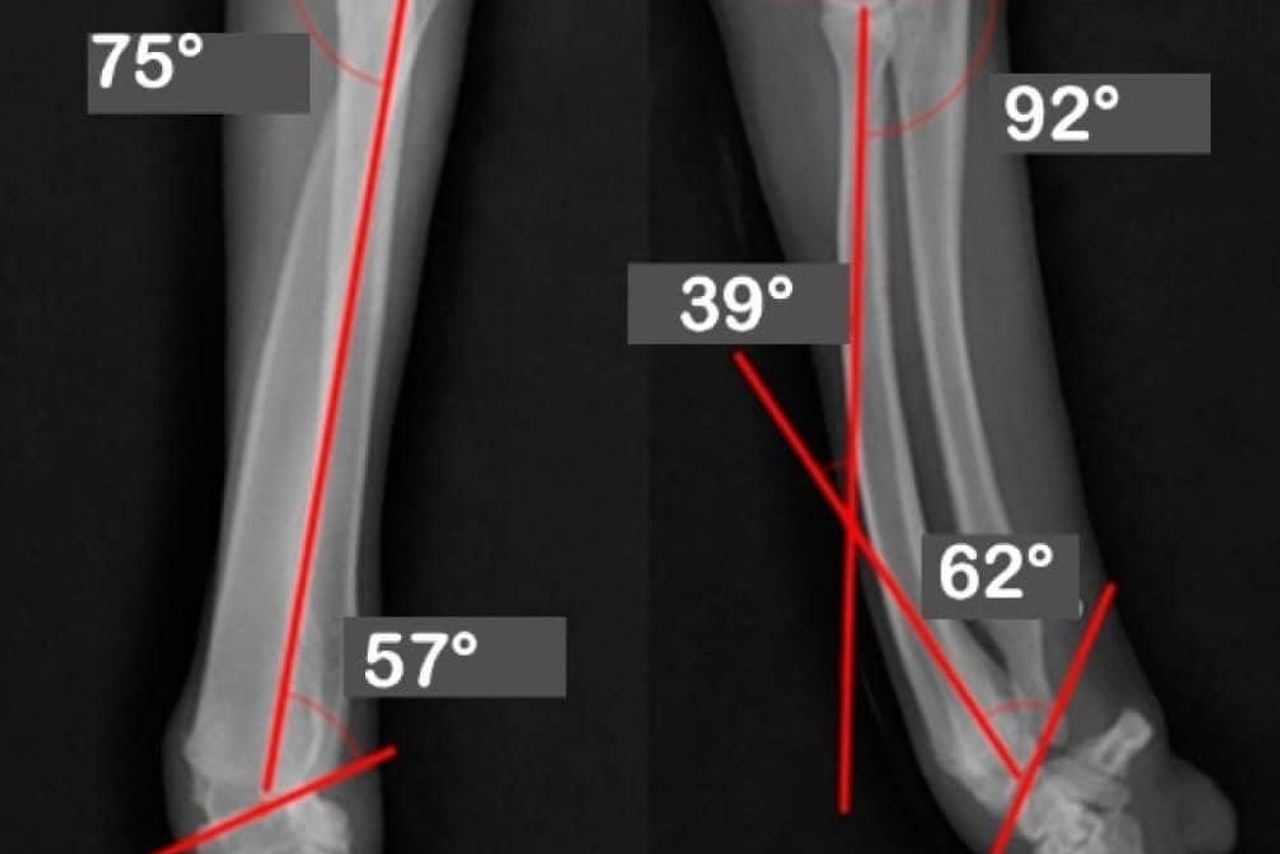

Кривое радио, также известное как лучевая кривизна, — ортопедическая аномалия, которая влияет на структуру радиокости...